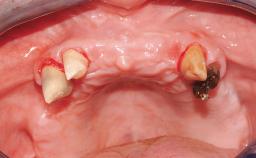

Immediate Loading of Eight Implants in the Maxilla and Six Implants in the Mandible and Final Restoration with Three-Unit and Four-Unit FDPs

Extensive scientific evidence has confirmed that immediately loaded implants with fixed full-arch provisional restorations can osseointegrate with success rates similar to conventionally or delayed loaded implants. A number of immediate-provisionalization techniques for edentulous jaws have been described. Some protocols differ when it comes to prefabricated provisional templates versus complete denture conversion; intrasurgical impressions versus direct relining; and cemented versus screw-retained provisional restorations. In this context, complete-denture conversion has been proposed for either intrasurgical impressions or direct relining. Another possibility is the utilization of a prefabricated provisional to be adapted either in the mouth (by direct relining) or in the laboratory (on a working model obtained from an intrasurgical impression).

Case Type Edentulous Maxilla

Defining Characteristics Fully edentulous upper jaw to be rehabilitated with four or more implants